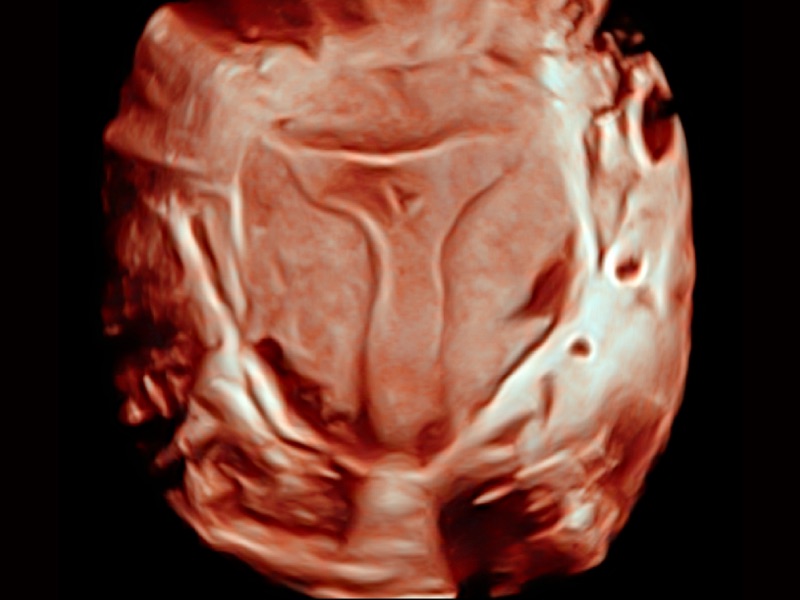

通过心肌识别技术和二维斑点追踪技术相结合,计算心肌各节段的应变应变率、速度、位移并以曲线图显示,实现整体或者局部心肌定量分析。同时可呈现牛眼图直观和准确诊断心肌的运动情况。

支持运动和药物负荷协议、多心动周期存储选择,为临床观察心肌负荷状态下的室壁节段运动、评估心肌缺血状态提供更多的解决方案。